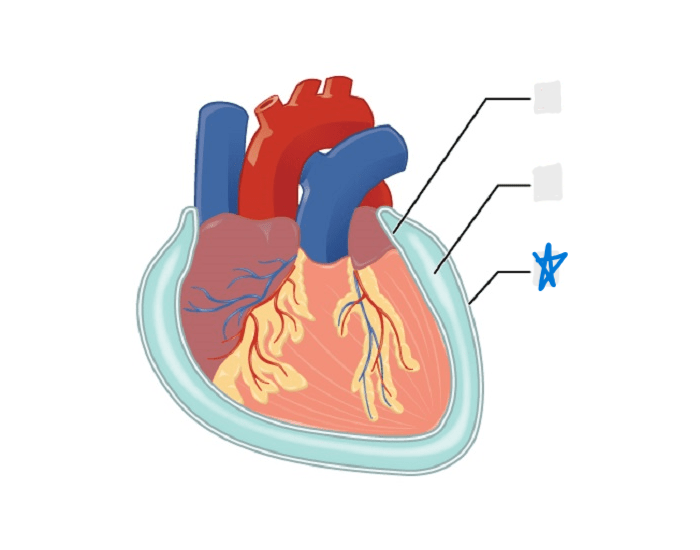

visceral pericardium

parietal pericardium

pericardial cavity